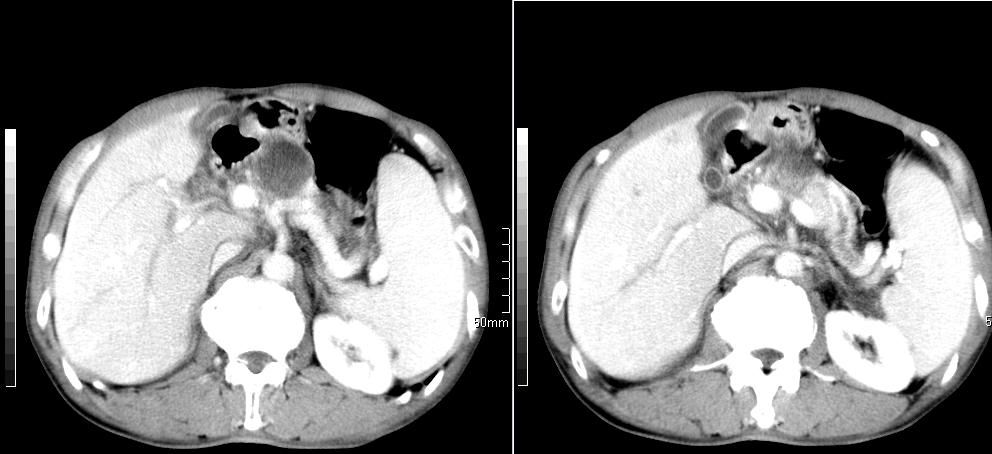

标题: CT26769:男,58岁,腹胀、腹部不适一年余 [打印本页]

标题: CT26769:男,58岁,腹胀、腹部不适一年余

肠系膜脂膜炎,胆囊炎,脾大。建议结合临床。鉴别:慢性胰腺炎并假囊肿形成。

1 慢性胰腺炎并假囊肿形成。2 慢性胆囊炎并累及肝边缘!

1)考虑慢性胰腺炎并假性囊肿形成。2) 慢性胆囊炎。3)肝内胆管扩张。

1肝内胆管扩张,性质待定,2慢性胰腺炎胰管扩张,胰腺颈部假囊肿,3肝左叶低密度为小囊肿,4胆囊炎。